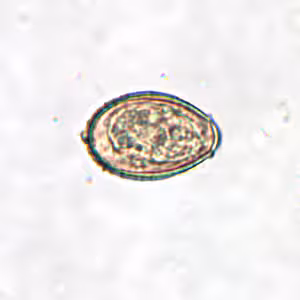

Clonorchis sinensis eggs.

Clonorchis sinensis eggs are small, ranging in size from 27 to 35 µm by 11 to 20 µm. The eggs are oval shaped with a convex operculum that rests on visible “shoulders” at the smaller end of the egg. At the opposite (abopercular) end, a small knob or hook-like protrusion is often visible. The miracidium is visible inside the egg. Eggs of C. sinensis are highly morphologically similar to Opisthorchis spp.